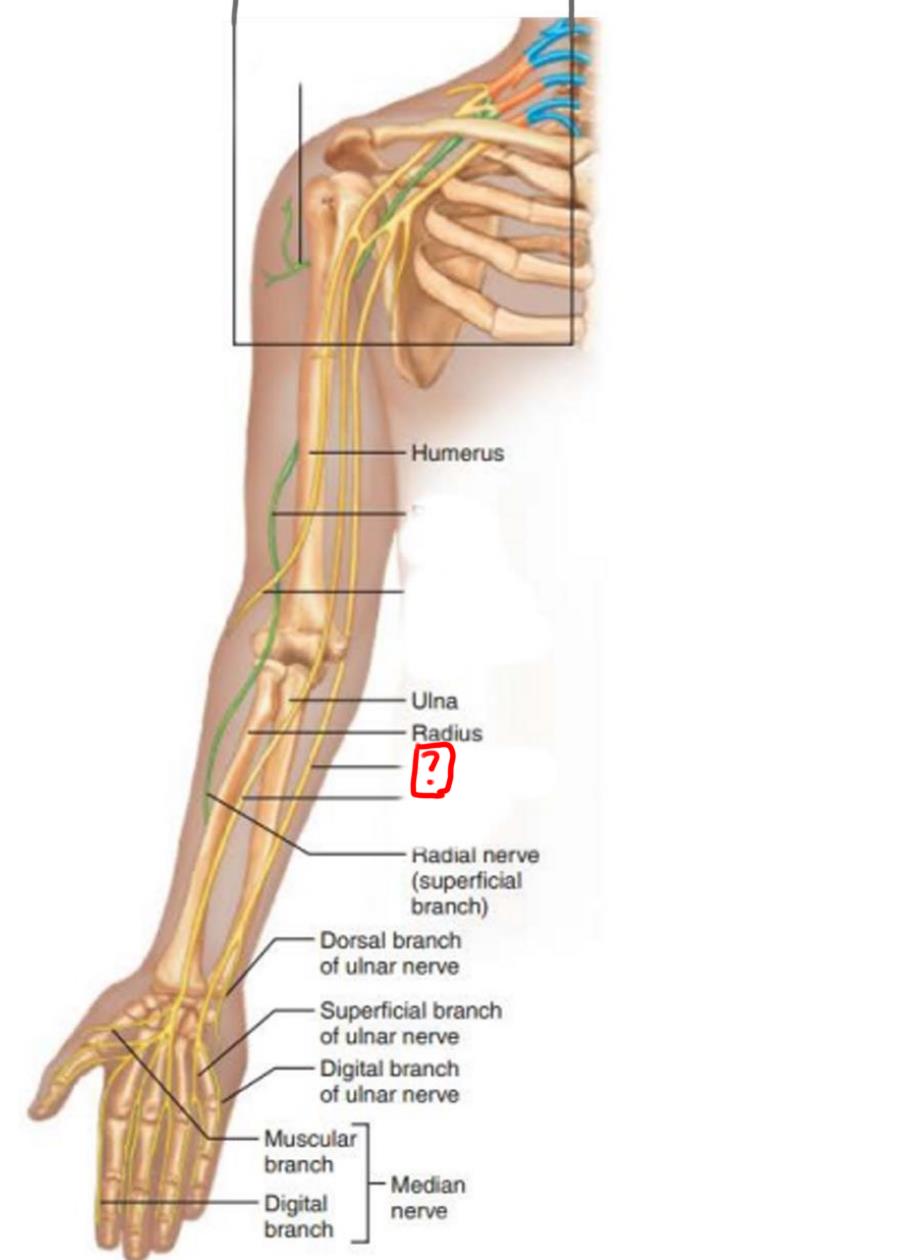

radial nerve

ulnar nerve

median nerve